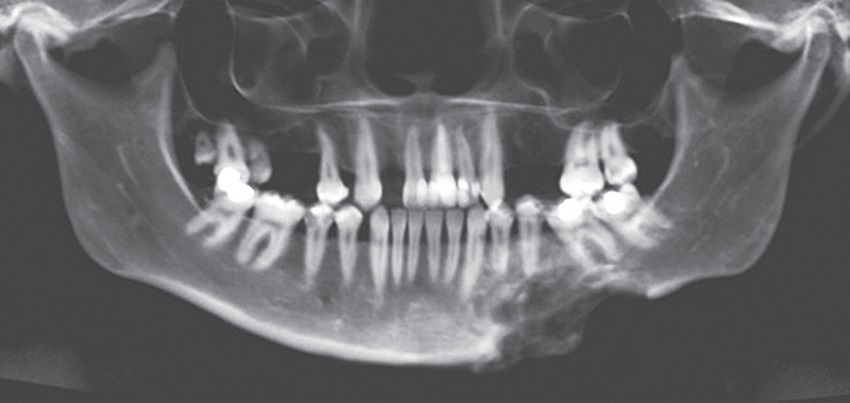

A 32-year-old female patient admitted in the Dental Department at the Hospital Batista Memorial with an slowgrowing increase in the region of left mandibular body volume and no painful symptoms (Figure 1A). Intraoral examination showed an increase in the volume with stony consistency, reduction in the depth of vestibular sulcus, discreet displacement of teeth 35 and 34 and integrity of the adjacent alveolar mucosa (Figures 1B and 1C). The image examination revealed multilocular osteolytic lesion, with cortical bone expansion, as well as discrete root resorption of the involved teeth (Figure 2). The patient underwent an incisional biopsy, which revealed proliferation of mesenchymal cells associated with an exuberant population of multinucleated giant cells and hemorrhagic foci (Figure 3). Tests for evaluating the serum levels of calcium, alkaline-phosphatase and parathyroid hormone were ordered and were within normal limits, ruling out Brown tumor of hyperparathyroidism (BTH), and the final diagnosis was CGCL. The patient underwent six intralesional applications, fortnightly, of 20 mg/ml triamcinolone hexacetonide diluted in anesthetic solution of 2% lidocaine/epinephrine 1:200.000 in a ratio of 1:1; 1 ml of the solution was infiltrated for each cm3 of the lesion. Radiographic follow-up revealed increased radiopacity, associated with a reduction of the lesion when compared to the initial radiographs. However, there was persistence of a bone callus in the region (Figure 4). One year after treatment completion, the patient performed osteoplasty of the mandible to improve the aesthetic and bone contouring. She has been under follow-up for five years, with no signs of recurrence.

Nogueira et al. (2010)(12) reported the use of intralesional corticosteroid therapy fortnightly, maintaining the number of six applications previously reported, allowing a better follow-up of the increase in opacification observed in the control radiographs. Similarly, in the case reported here, intralesional injections of triamcinolone hexamethonide, a long-acting corticosteroid, were performed in a protocol of six biweekly applications and, subsequently, the radiopacity increase in the region affected by the lesion was observed radiographically.